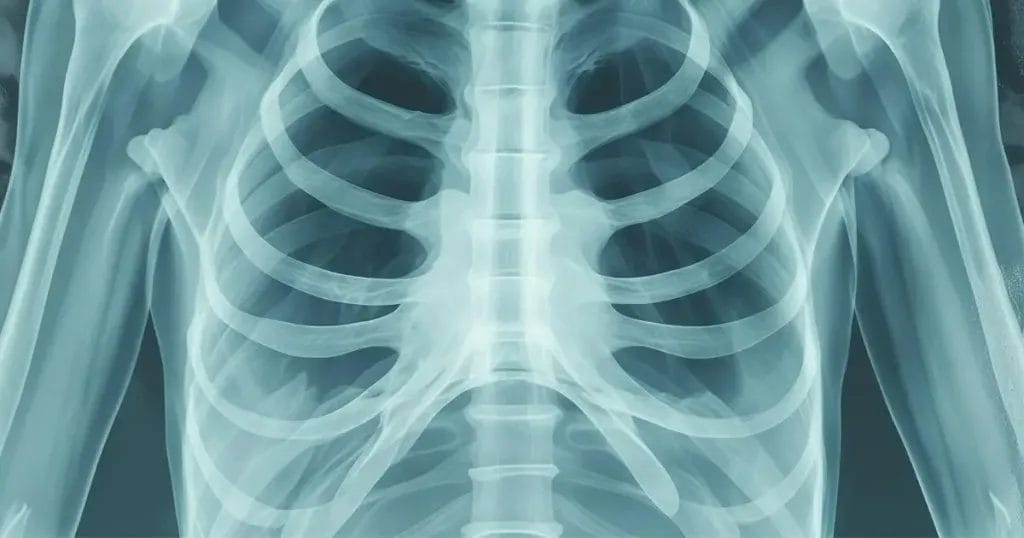

متى يلتئم القفص الصدري بعد عملية القلب المفتوح؟ هو سؤال يشغل بال العديد من المرضى الذين أجروا تلك الجراحة حيث يتطلب الشفاء من عملية القلب المفتوح مدة طويلة قد تستغرق شهورًا أو سنوات، وتجري عملية القلب المفتوح من خلال إجراء شق جراحي عبر الصدر، و يتضمن ذلك قطع عظمة القص طوليًا للوصول إلى القلب.

وفي نهاية العملية، تثبت عظمة القص بواسطة عدد من الأسلاك الفولاذية التي عادةً ما تبقى في مكانها لبقية حياة المريض. في هذا المقال سنوضح متى يلتئم القفص الصدري بعد عملية القلب المفتوح؟، فتابع معنا.

يبلغ طول جرح الصدر حوالي 12 إلى 18 سم، بالنسبة لمعظم الناس، تبدأ عظمة القص بالالتحام خلال أسبوعين إلى ثلاثة أسابيع بعد الجراحة، و بعد أربعة أسابيع، تبدأ بالتحول إلى جسر عظمي أكثر صلابة وثباتًا، في هذه المرحلة، يبدأ المريض بالشعور بألم أقل ويمكنه البدء بممارسة أنشطة خفيفة.

بحلول الأسبوع السادس إلى الثامن، تكتسب عظمة القص حوالي 50% إلى 60% من قوتها الطبيعية، و يستمر العظم في إعادة تشكيله وتصلبه خلال الأسبوع الثامن إلى الثاني عشر، حيث تلتئم عظمة القص تمامًا بعد 12 أسبوعًا، لأنه بعد الجراحة، يستخدم الجراح سلكًا قويًا لتثبيت العظام المقطوعة معًا، مما يسمح بنمو خلايا جديدة، وعلى مدار أشهر، تلتحم العظام مجددًا.

يلتئم القفص الصدري تماما بعد مرور 3 أشهر من إجراء عملية القلب المفتوح وتستمر العظام في التحسن لمدة قد تصل إلى 6 أشهر.